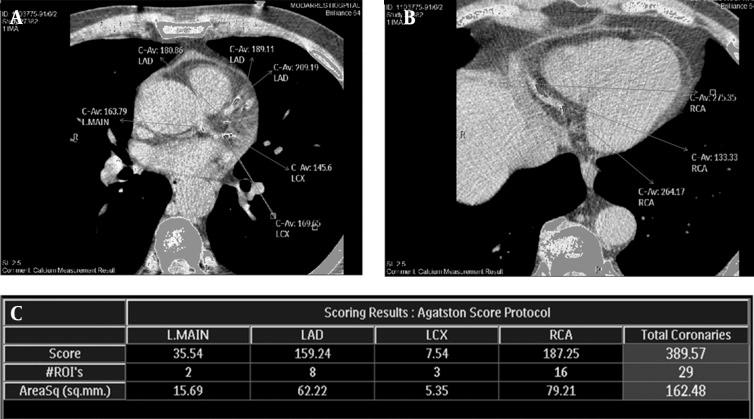

冠状动脉钙化评分:综述

Coronary artery calcium score: a review.

Radiology Department, Modarres Hospital, Shahid Beheshti University of Medical Sciences, Tehran, IR Iran ; Advanced Diagnostic and Interventional Radiology Research Center (ADIR), Tehran, IR Iran.

Iran Red Crescent Med J. 2013 Dec;15(12):e16616. doi: 10.5812/ircmj.16616. Epub 2013 Dec 5.